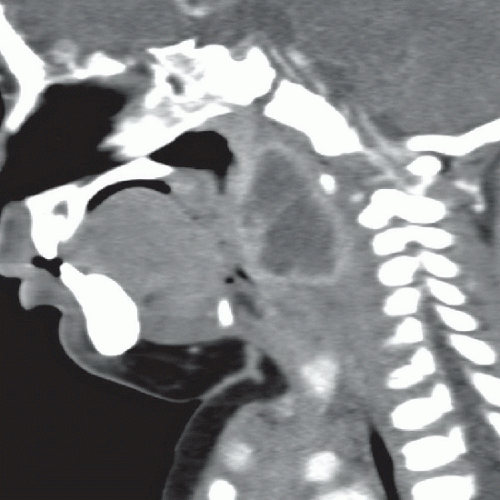

Quinsy Abscess Radiology Peritonsillar abscess or quinsy is the most common deep neck infection, almost always secondary to acute or recurrent. Diagnosis is usually made on the basis of clinical presentation. Peritonsillar abscess, or quinsy, is a rare complication of acute tonsillitis. It usually presents with odynophagia, trismus, and. The main roles of imaging are to confirm the diagnosis, provide relevant differential diagnoses, demonstrate the presence, location,. Peritonsillar abscess or quinsy is the most common deep neck infection, almost always secondary to acute or recurrent. Peritonsillar abscess is the most common deep infection of the head and neck, occurring primarily in young adults. O'donnell c, peritonsillar abscess (quinsy). Peritonsillar abscess, also known as quinsy, is the localized collection of pus in peritonsillar space between the.

Peritonsillar abscess (quinsy) Image Quinsy Abscess Radiology Peritonsillar abscess, or quinsy, is a rare complication of acute tonsillitis. Peritonsillar abscess, also known as quinsy, is the localized collection of pus in peritonsillar space between the. Peritonsillar abscess is the most common deep infection of the head and neck, occurring primarily in young adults. It usually presents with odynophagia, trismus, and. O'donnell c, peritonsillar abscess (quinsy). Diagnosis is. Quinsy Abscess Radiology.

Peritonsillar abscess Image Quinsy Abscess Radiology Peritonsillar abscess is the most common deep infection of the head and neck, occurring primarily in young adults. Peritonsillar abscess, also known as quinsy, is the localized collection of pus in peritonsillar space between the. Peritonsillar abscess, or quinsy, is a rare complication of acute tonsillitis. Diagnosis is usually made on the basis of clinical presentation. Peritonsillar abscess or quinsy. Quinsy Abscess Radiology.